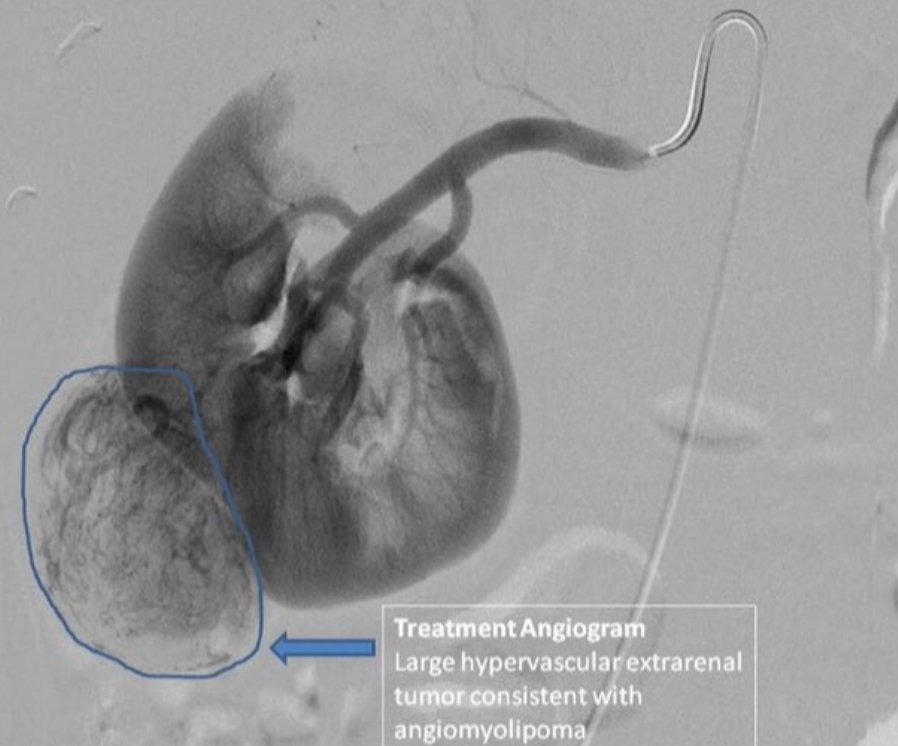

▪︎ من أهم المضاعفات التي قد تسببها هذي الأورام هو النزيف المفاجئ من الكلية وهي تعتبر من الحالات الخطيرة جدا ...

▪︎ متى يجب على الطبيب معالجة هذي الأورام :

١▪︎إذا تجاوز حجم الورم ٤ سم ..

٢▪︎إذا سبب ألم للمريض ..

٣▪︎في حالة حدوث نزيف من الورم ..

تتم معالجة هذي الأورام في الغالب عند طريق الأشعة التداخلية و إغلاق الأوعية الدموية المغذية للورم ..